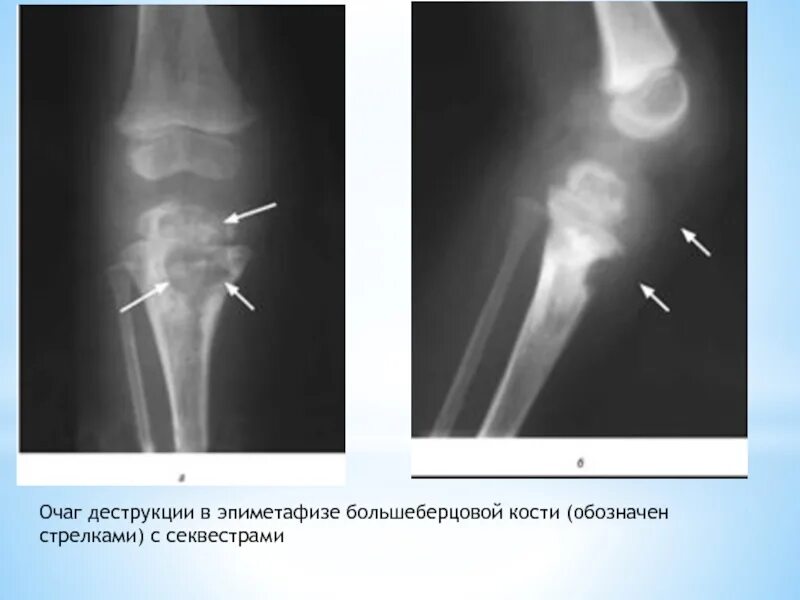

Зона деструкции